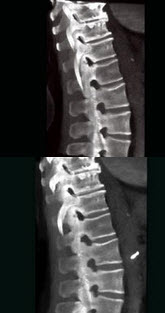

37、单项选择题

女,65岁,腰背部疼痛,僵硬半年余,结合影像学检查,最可能的诊断是()

A.脊椎肿瘤

B.椎体压缩性骨折

C.化脓性脊柱炎

D.强直性脊柱炎

E.脊椎退行性变